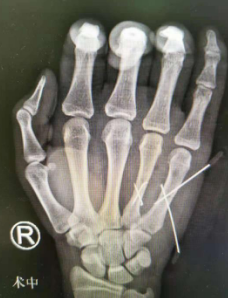

我院急诊科通知手外四病区的值班医疗小组接诊,建议患者办理住院手续尽快手术。强强的妈妈说,6月18日强强要参加中考,不能耽误,她必须把这个特殊的情况向医生说明。接诊的医生介绍,强强右手第4、5掌骨骨折,其他部位未受伤。如果手术,术后两三天内不能完全消肿,可能会影响中考;如果不在24小时内手术,可以选择5-7天左右消肿后再手术。延缓手术肯定会影响恢复,但是从强强目前的情况考虑,先中考,再手术是比较好的选择,男子汉大丈夫,忍一忍疼痛应该是没问题的。强强当即决定出院,好好准备中考。出院前,医生帮他用夹板外固定骨折。

6月20日中考结束,强强和妈妈就再次来到了医院,并于当天下午进行了右手第4、5掌骨骨折切开复位内固定手术。手术非常顺利,术后第二天强强还用双手打起了游戏。